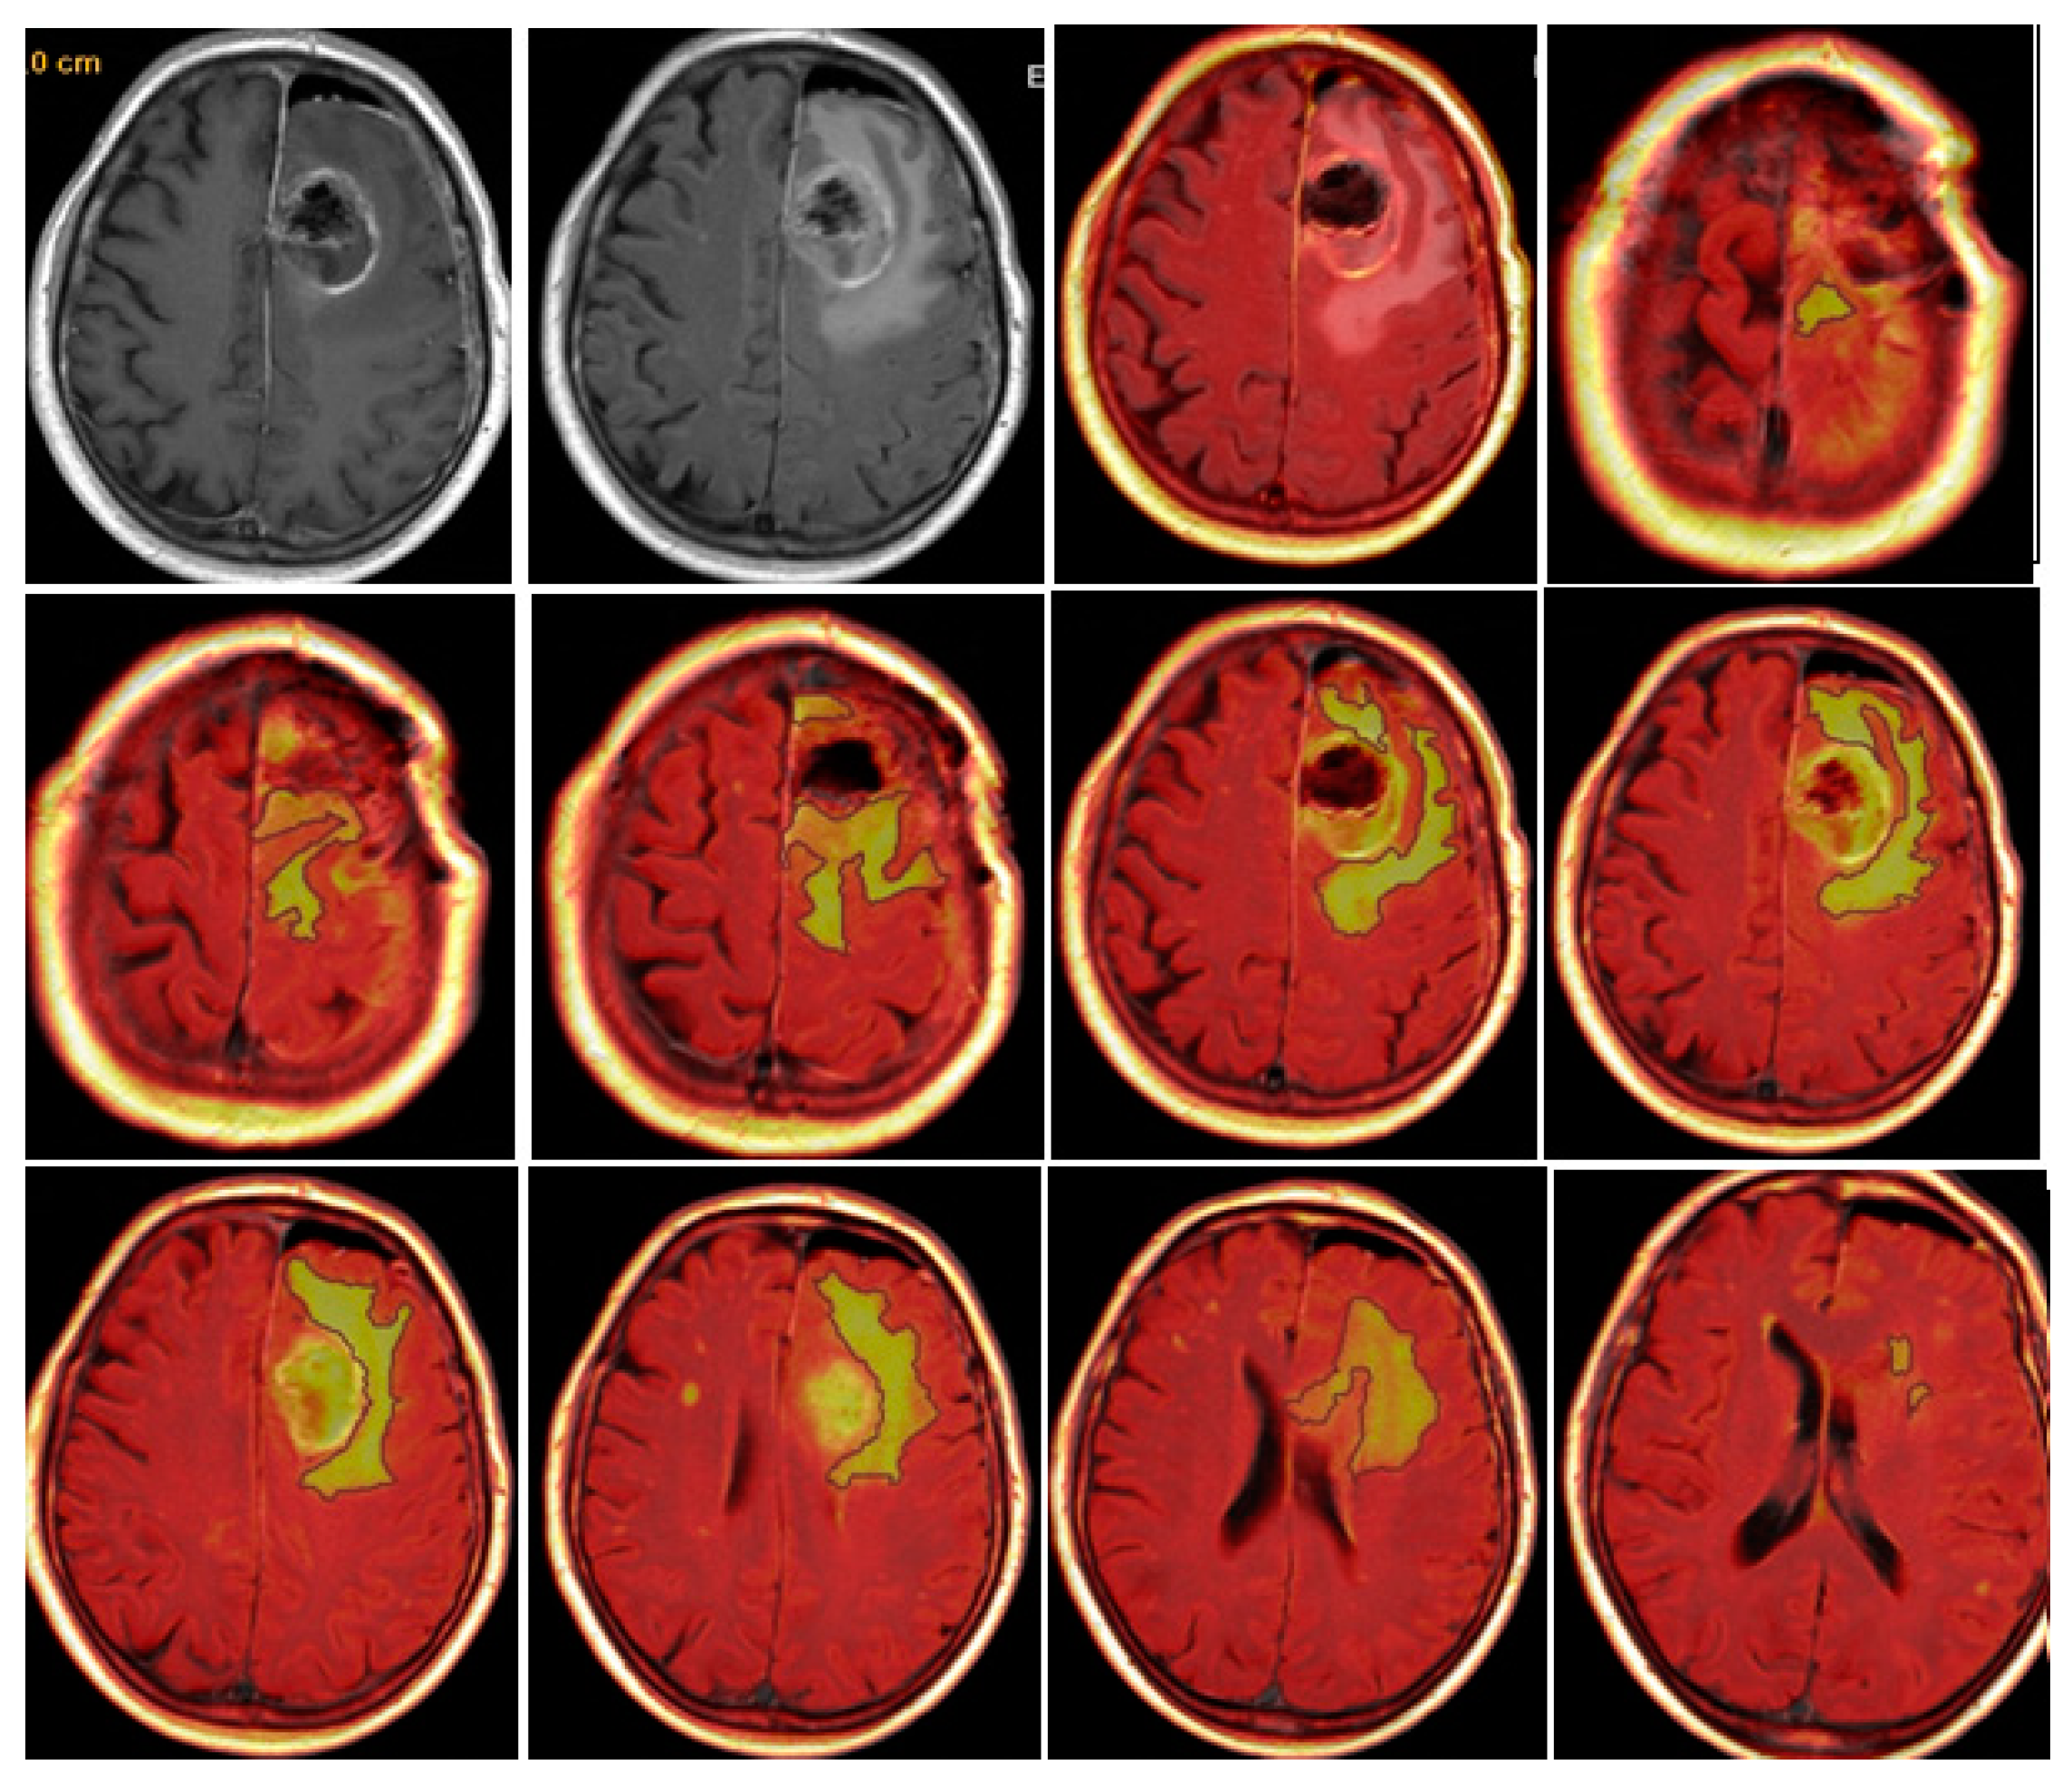

CE-PTV was evaluated on 2D axial Contrast Enhanced T1 weighted (CE-T1w) images (slice thickness: 5 mm.; slice spacing: 5,5-6 mm.), by contouring manually enhanced tumor areas on every single axial slice, excluding necrosis; the same analysis was subsequently performed with semi-automatic method by using the apposite tool of the AW server 3.2 [Figure 1 and Figure 2].

CE-RTV was assessed on 2D axial CE-T1w images (slice thickness: 5 mm.; slice spacing: 5,5-6 mm.), achieved with subtraction imaging technique to minimize errors due to the spontaneous hyperintensity of degradation products of hemoglobin or related to the presence of haemostatic/chemotherapeutic agents in the surgical area. As for CE-PTV, the analysis was performed both manually and semi-automatically [Figure 3 and Figure 4].

T2/FLAIR-PV and T2/FLAIR-RV were both evaluated manually on axial hybrid sequences resulting from FLAIR (slice thickness: 5 mm.; slice spacing: 5,5 mm.) and CE-T1w (slice thickness: 5 mm.; slice spacing: 5,5-6 mm.) fusion, in order to measure exclusively the edema/infiltration component, excluding the tumor enhancing mass previously assessed with CE-PTV and CE-RTV measurements [Figure 5 and Figure 6].

Figure 1. CE-PTV manual evaluation.

Figure 2. CE-PTV semi-automatic evaluation.

Figure 3. Contrast Enhancement Postoperative Tumor Volume (CE-RTV) manual evaluation.

Preprints 86216 g003

Figure 4. Contrast Enhancement Postoperative Tumor Volume (CE-RTV) semi-automatic evaluation.

Preprints 86216 g004

Figure 5. Edema/Infiltration Preoperative Volume (T2/FLAIR-PV).

Preprints 86216 g005

Figure 6. Edema/Infiltration Postoperative Volume (T2/FLAIR-RV).

Preprints 86216 g006